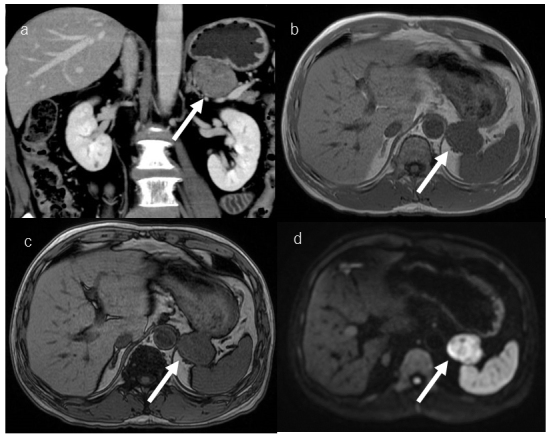

Meta-iodobenzylguanidine (MIBG) is an analog of norepinephrine and guanethidine, and MIBG scintigraphy is useful to diagnose tumors of the sympathetic nervous system, such as pheochromocytoma, paraganglioma, and neuroblastoma. To date, there have been few reports of MIBG accumulation in gastrointestinal stromal tumors (GISTs), so the mechanism and frequency of MIBG accumulation in GISTs are unknown. Herein, we report and discuss three cases of GIST in which scintigraphy that was performed to exclude pheochromocytoma showed MIBG accumulation.